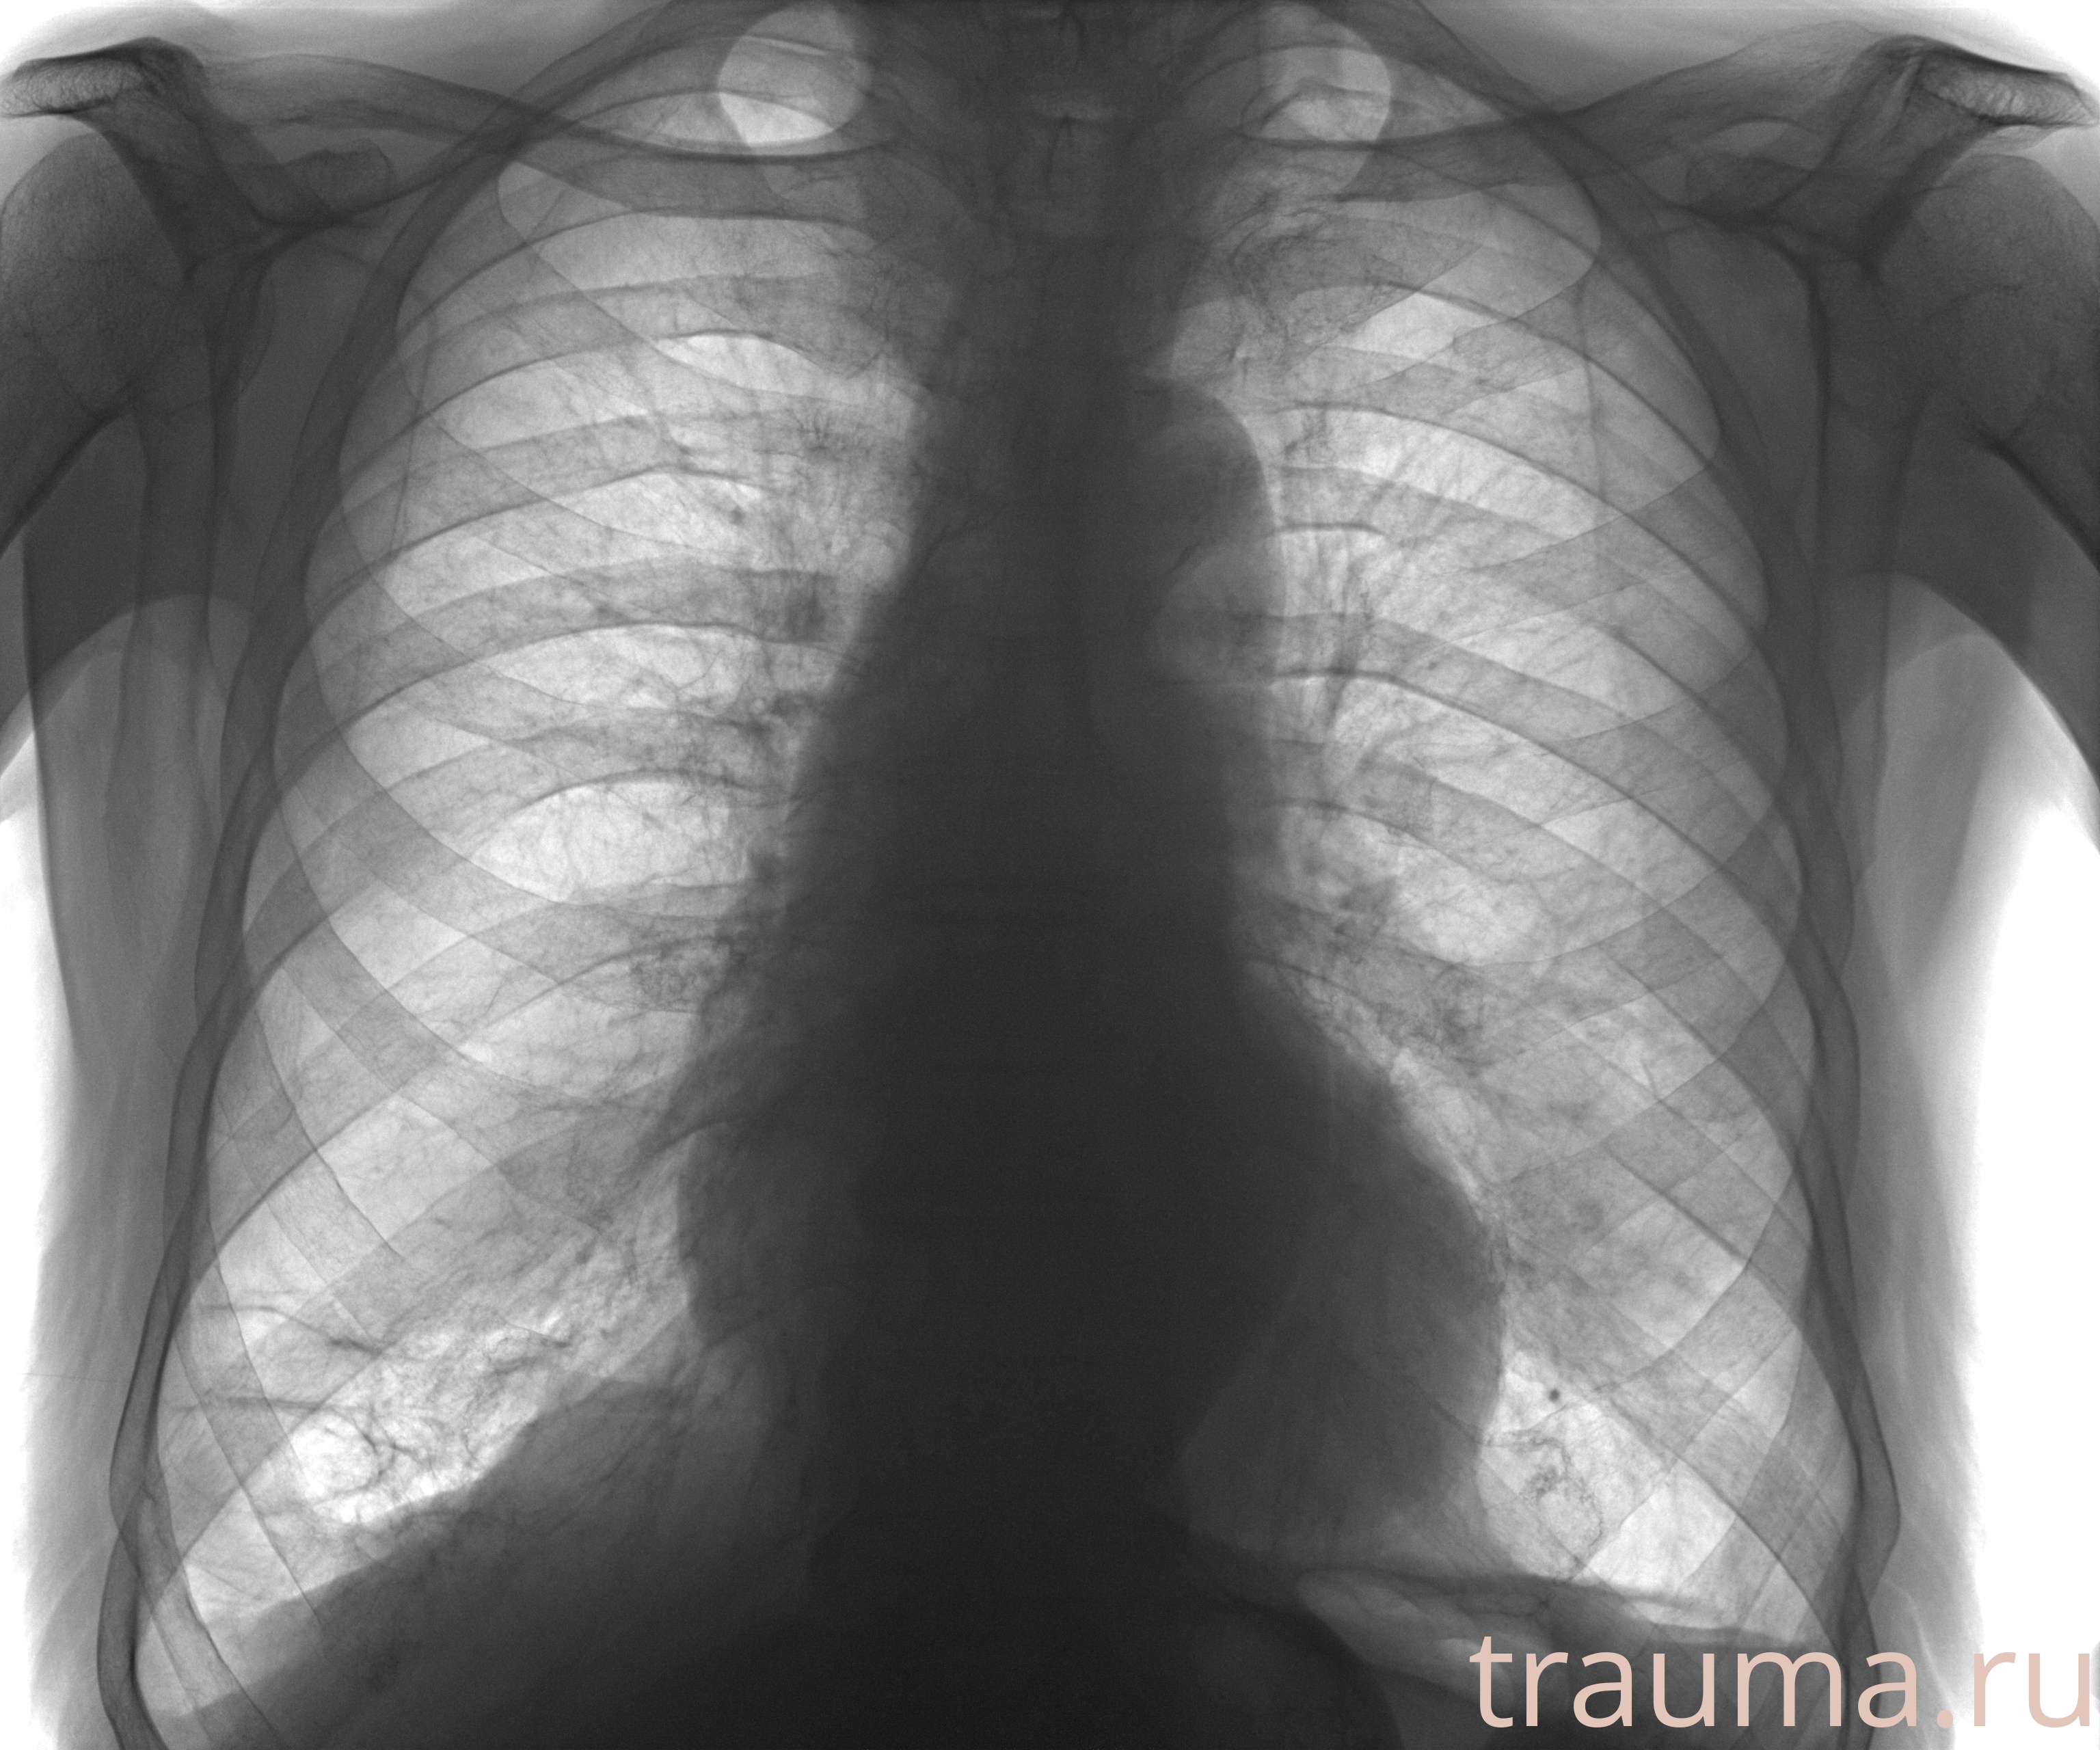

Рентген на дому: по вашему адресу приезжает врач-рентгенолог, травматолог-ортопед с мобильным рентгеновским аппаратом, проводит диагностику травмы или заболевания, делает необходимые рентгенограммы, дает рекомендации по дальнейшему лечению. Получить качественные снимки в домашних условиях возможно благодаря уникальной методике, разработанной МосРентген Центром для института  Склифосовского

при переломе шейки бедра и пневмонии от компании МосРентген Центр - партнера Института имени Склифосовского